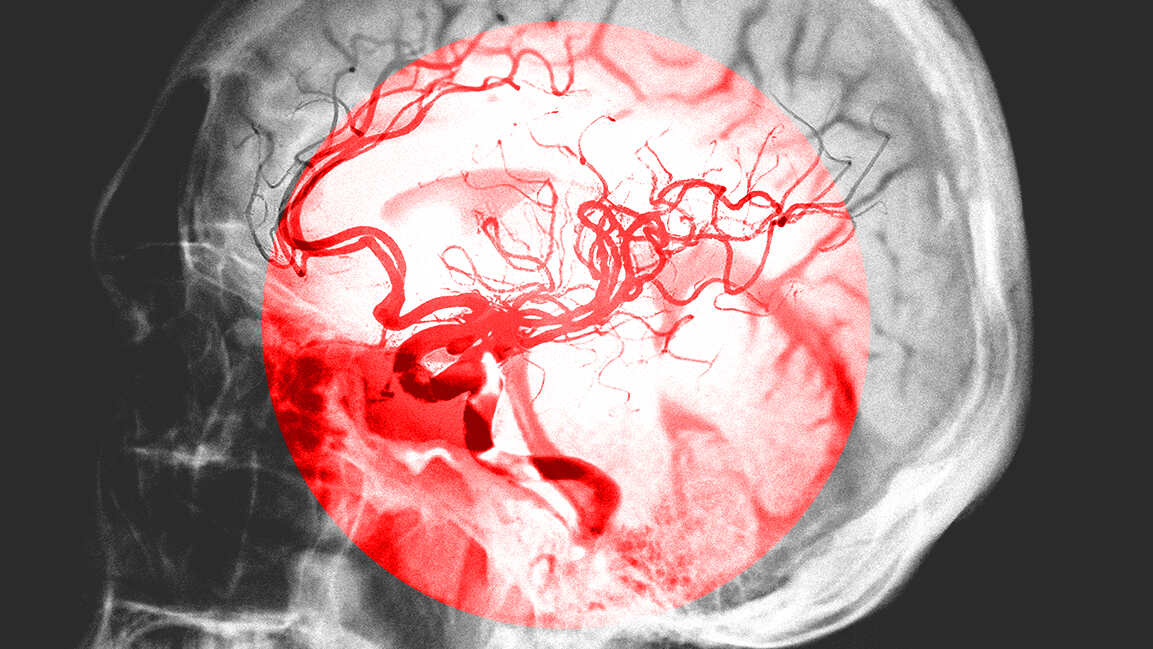

Here’s how Cleveland Clinic Abu Dhabi is innovating brain aneurysm treatment

The first patient treated with the device showed successful aneurysm closure within three months.

Cleveland Clinic Abu Dhabi has carried out the region’s first procedure using the Artisse Intrasaccular Flow Modulator, an advanced implant designed to treat wide-necked brain aneurysms.

The minimally invasive treatment uses a catheter to place a mesh device that seals the aneurysm, lowering the risk of rupture and stroke. The first patient treated with the device showed successful aneurysm closure within three months.

Fayeza Al Yafie, Executive Director of Healthcare Quality at the Department of Health – Abu Dhabi, said the achievement underscores the emirate’s focus on innovation and high-quality patient care.

Khalil Zahra, Staff Physician in Neurosurgery at Cleveland Clinic Abu Dhabi, noted that the technique improves treatment options for complex aneurysms while minimizing the need for invasive surgery.